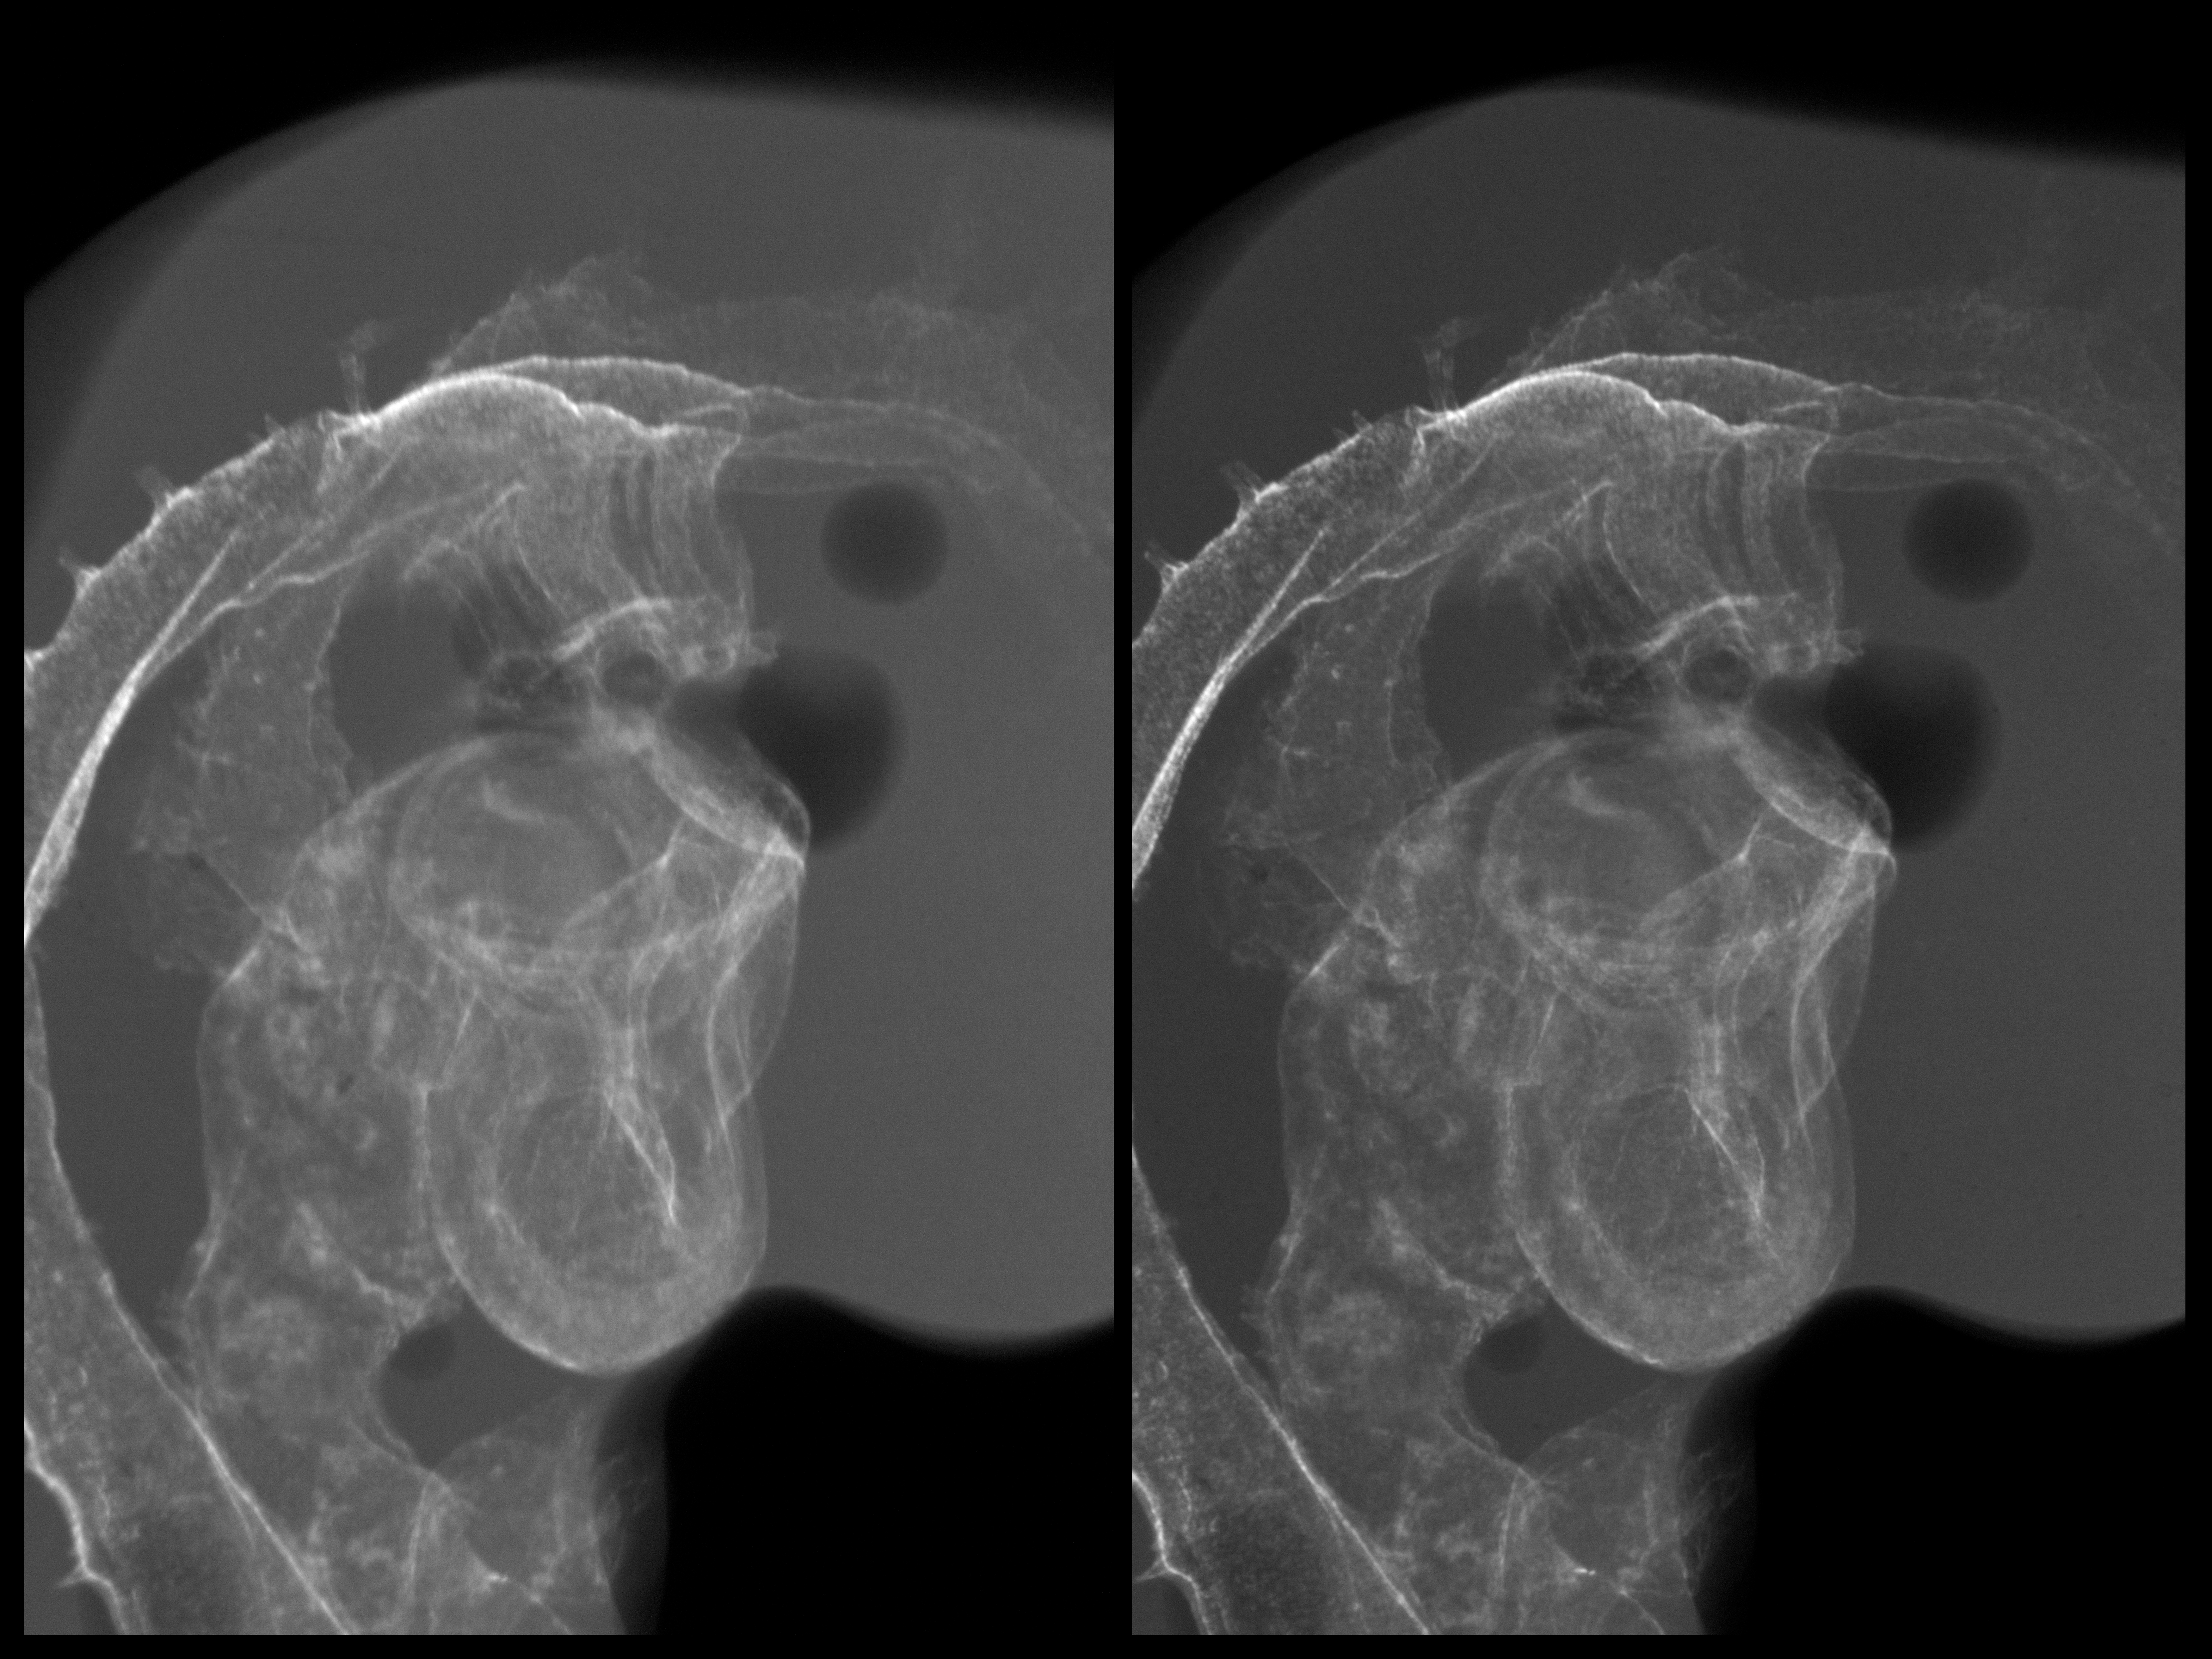

Chick Embryo Microangiography

Hamburger-Hamilton (HH) Stage 20 (approx. 3 - 3.5 days)

Stereo X-Ray Micrographs